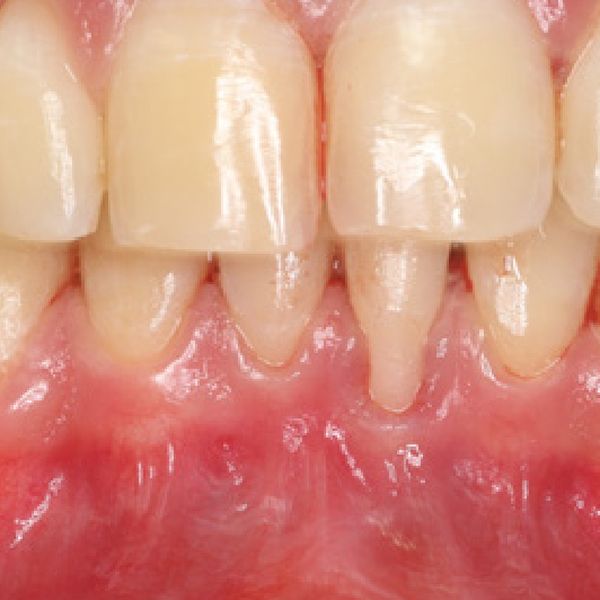

Anamnesi patologia: il paziente si presenta alla nostra osservazione lamentando sensibilità dentale a carico del 31. Dopo visita Parodontale e sondaggio si evidenzia una recessione di prima classe a carico dell’elemento 31, inoltre alla trazione del labbro, si manifesta la presenza di un frenulo labiale inferiore accessorio che agisce sul margine gengivale, probabile causa della recessione stessa.

A tre giorni dall’intervento si evidenzia un’avanzata riepitelizzazione ed un leggero recupero della recessione.